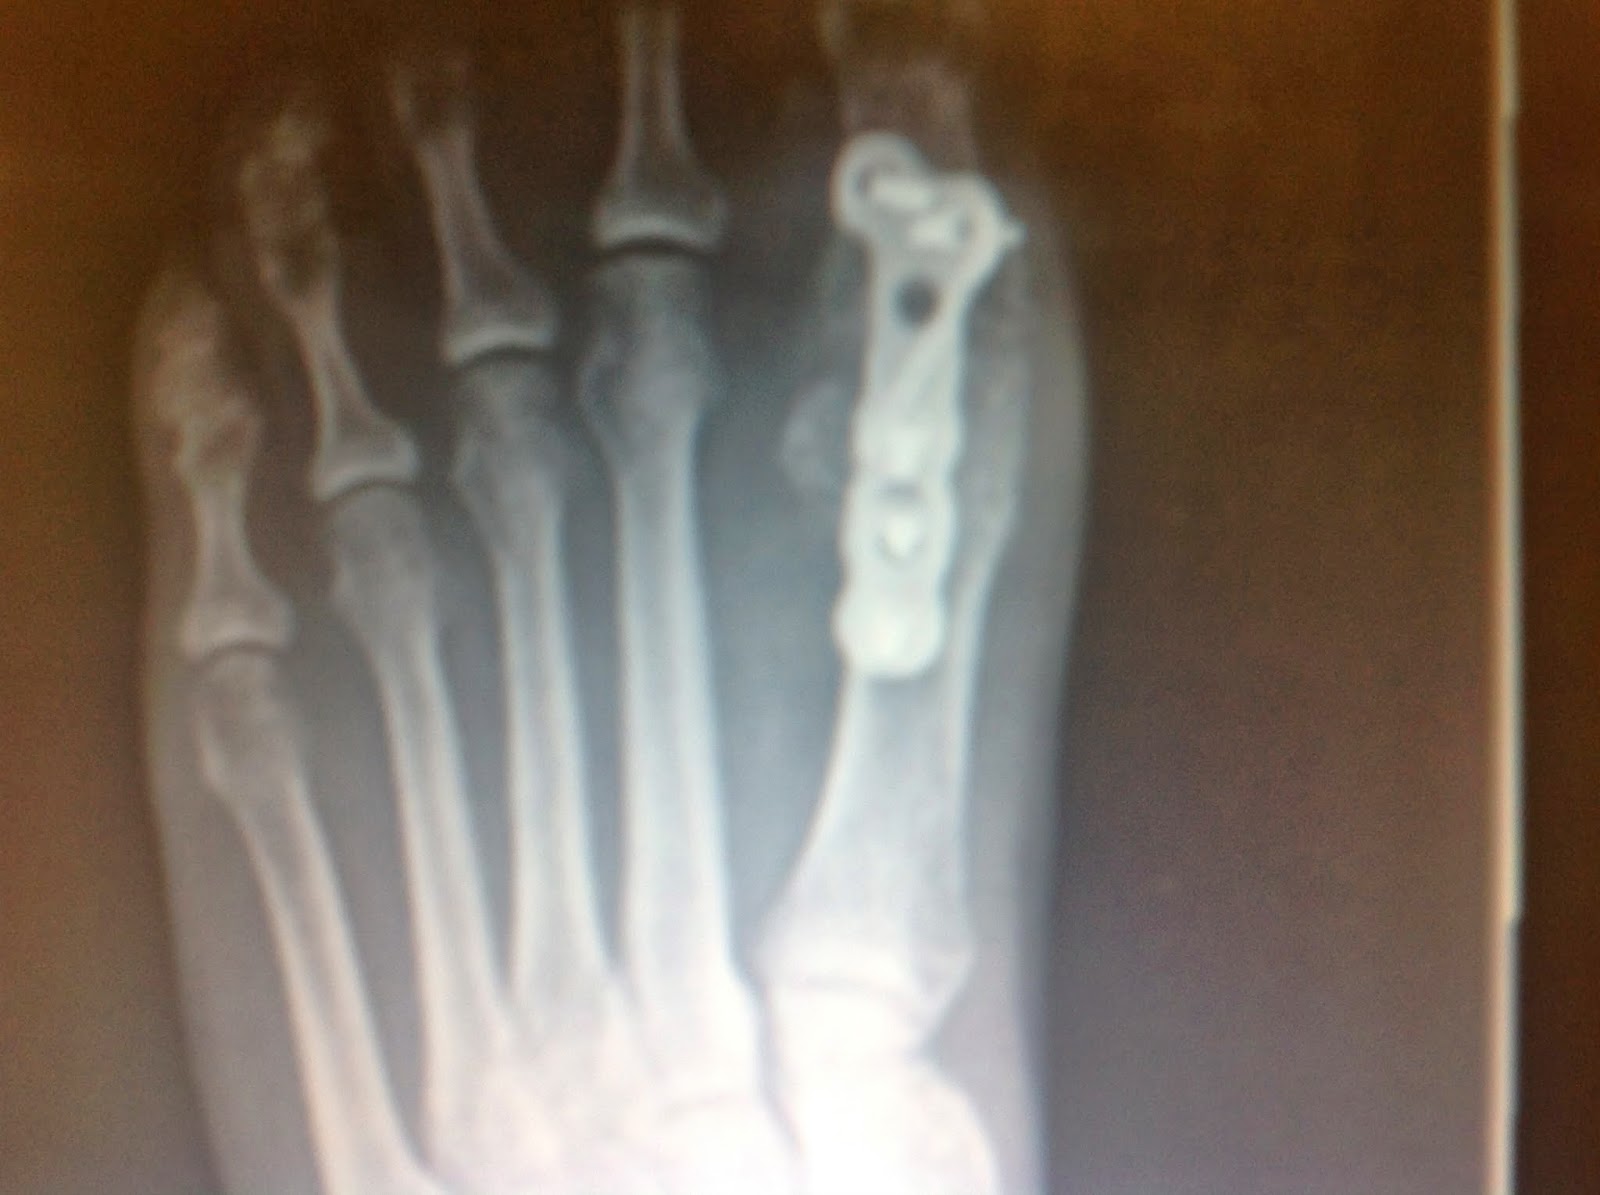

First MTP Joint Fusion (Locking Plate) California Orthopaedic Specialists Toe Joint Fusion Pain The invasive procedure is extremely helpful in correcting toe malformation and reducing pain in the metatarsophalangeal joint. In a first mtp joint fusion, the bones are joined (fused) together permanently so they cannot rub against each other and cause pain. Call your doctor now or seek immediate. This procedure is performed to straighten the joint or joints of the toe.. Toe Joint Fusion Pain.